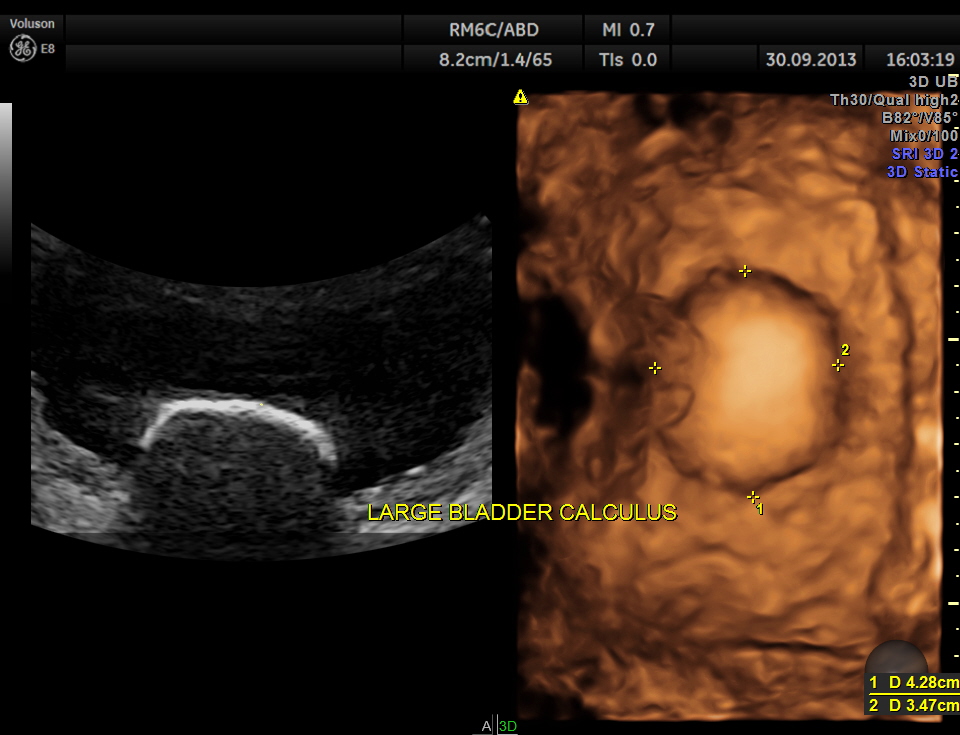

urinary bladder showed a large calculus and prominent swelling of the median lobe of the prostate.

2 D and 3 D of the bladder calculus alone.

The diagnosis given was Large calculus in the urinary bladder , Severe prostatic enlargement with prominent median lobe hypertrophy , causing Right sided obstructive uropathy.

The diagnosis was made with the 2D images , but the 3 D images were very helpful in explaining to the patient.